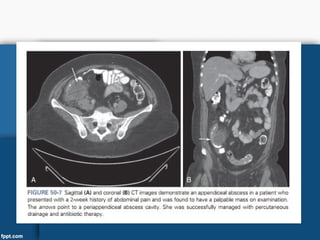

Delayed Presentation of Appendicitis

• Patients may occasionally present several days to even

weeks after the onset of appendicitis.

• Fluid resuscitation is initiated, and broad-spectrum

antibiotic therapy is initiated.

• CT scan is obtained, and perforated appendicitis with

a localized abscess or phlegmon is confrmed